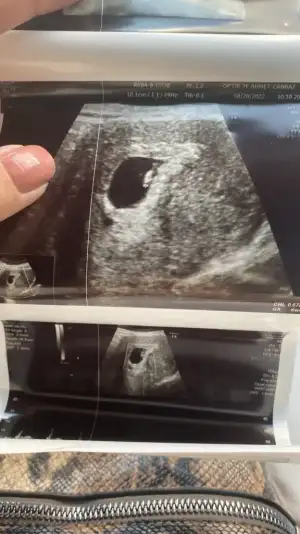

Kız benide ağlatdın..İn şa Allah bizlerde duyarız kuzumKızlar çıktım doktordan ayy şükürler olsun gayet iyiyiz kalp atıslarını duyduk allah ım nasıl bir duygu eşim agladıbende panik atak var benim kalp yerinden cıkcak doktor ddi bebekten cok suan senin kalp atıslarını duyuyorum dedi

bu da minnosun resmi karından baktı ramzi teorisine bakın 3. Kare

7 eylülde bidaha cagırdı ense kemik omurgalarına bakalım dedi tekrar idrar testi verdim bide kan verdim gene baska değerlerede bakıcam ddi

Oyy ne kadar tatlı duruyor ordaKızlar çıktım doktordan ayy şükürler olsun gayet iyiyiz kalp atıslarını duyduk allah ım nasıl bir duygu eşim agladıbende panik atak var benim kalp yerinden cıkcak doktor ddi bebekten cok suan senin kalp atıslarını duyuyorum dedi

Maşallah çok sevindim adınaKızlar çıktım doktordan ayy şükürler olsun gayet iyiyiz kalp atıslarını duyduk allah ım nasıl bir duygu eşim agladıbende panik atak var benim kalp yerinden cıkcak doktor ddi bebekten cok suan senin kalp atıslarını duyuyorum dedi